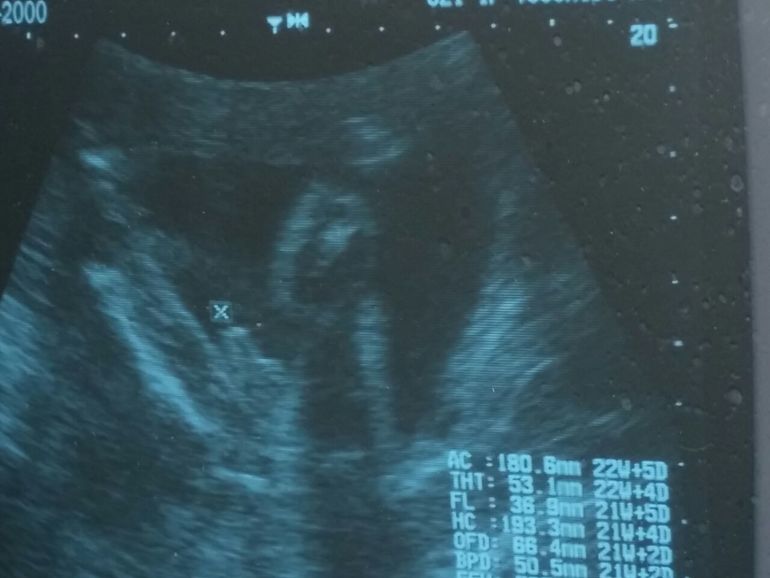

Вчера у нас было Узи)) 15 неделя ...Сказали пол))) Как вы думаете, кто это?))))

да, со всех ракурсов посмотрели)))) везде гладенько) Неделю назад тоже пуповинкой закрывалась))

У вас девочка, у нас в 15 недель огурчик большой, а тут все чисто.Поздравляем с дочкой!!!

Мне кажется девочка. у меня с обеими так было чистенько. Вот сейчас сразу фото врач дал и крестиком пометил "огурчик"